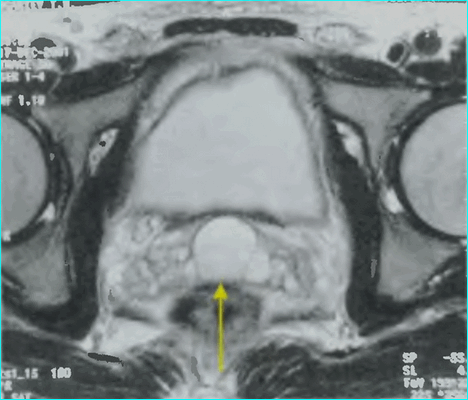

МРТ: рак простаты Т2а и Т3а (стрелки указывают на вовлеченность капсулы в опухолевый процесс)

А - магнитно-резонансная томограмма демонстрирует неровность контура капсулы левой доли простаты с распространением мягкотканного компонента за ее пределы (стрелка), Т2 ВИ. В - изображение после динамического введения гадолиния. С - после обработки компьютерной программой - явное усиление интенсивности МР-сигнала в зоне патологии, типичное для неопластического перерождения